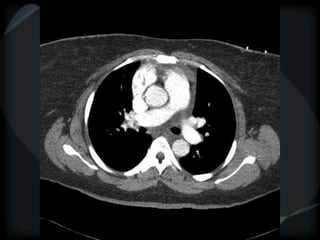

PHTN – PA 39mm

39.2mm

PHTN and septal thickening

? PVOD